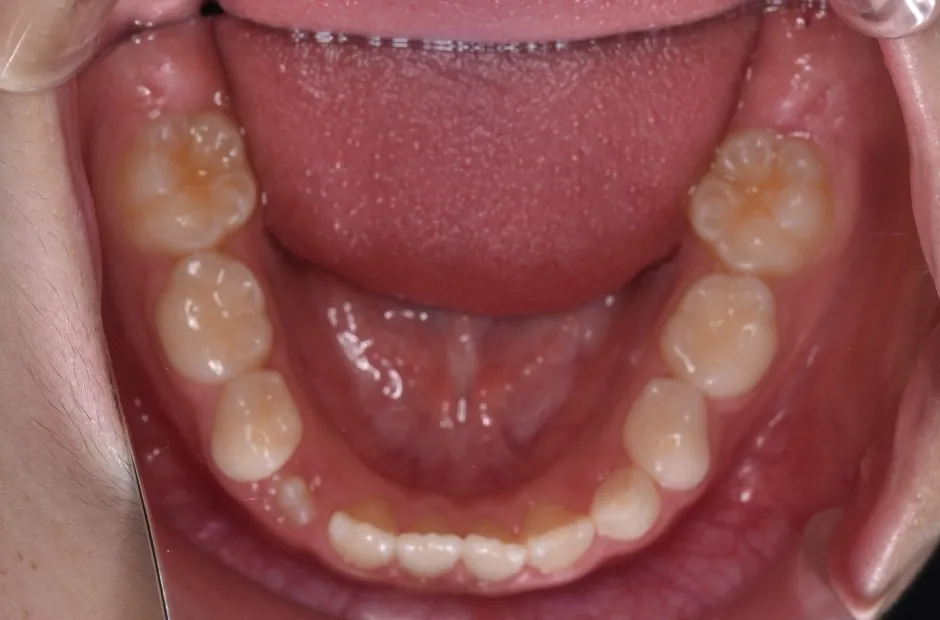

叢生

| 診断名・主訴 | 叢生 |

|---|---|

| 年齢・性別 | 10歳・女性 |

| 治療期間・回数 | 2年半 |

| 治療に用いた主な装置 | 拡大床装置 |

| 抜歯部位 | なし |

| 治療費 | 30万円(税抜) |

| リスク・副作用 | 装置による違和感・疼痛・歯肉退縮・歯根吸収・虫歯のリスクなど |

治療前

治療中

治療後